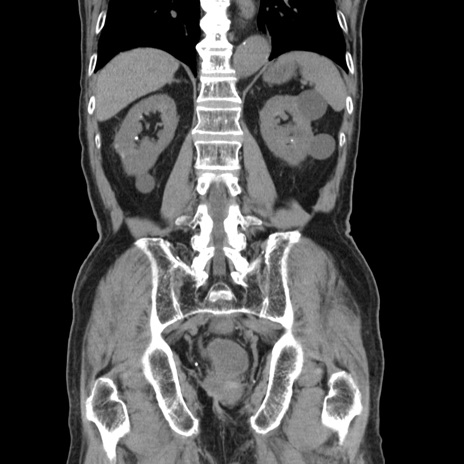

症例24(冠状断像)

【症例】80歳代男性

【主訴】左側腹部痛、嘔吐

【現病歴】本日早朝より左腹部に痛みあり。昼頃嘔吐認めたため、救急要請。

【既往歴】直腸癌(Mile手術)、胆摘

【身体所見】意識清明、BT 35.9℃、BP 221/93mmHg、SpO2 97%(RA) 、腹部:左ストーマ周囲に限局性の腹部膨隆あり。 膨隆部自発痛・圧痛あり・軟。

【データ】WBC 7700、CRP 0.09